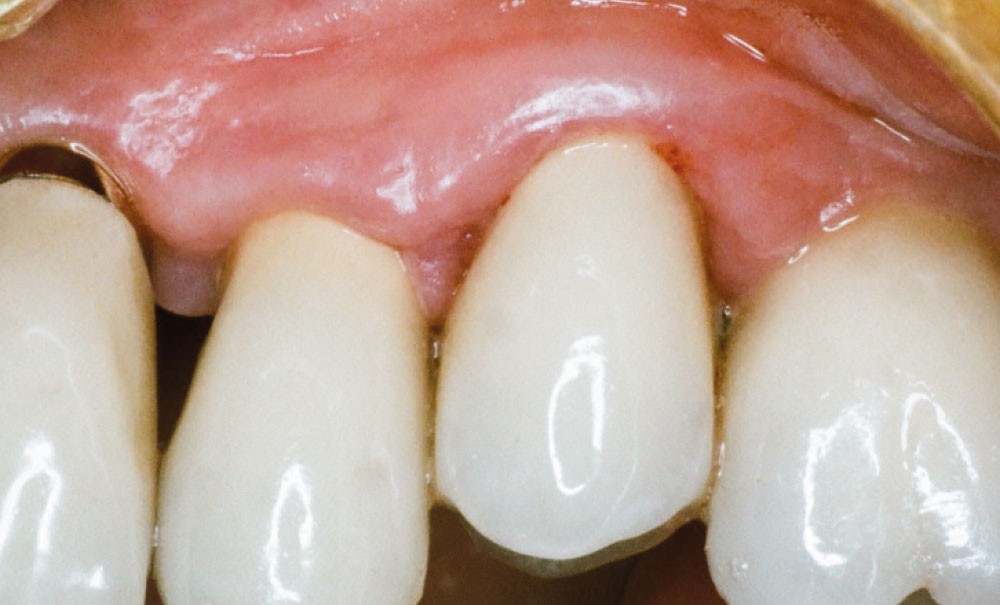

En mars 2016, la patiente se plaint d’une sensibilité sur la 25 et on note cliniquement une inflammation gingivale associée à un décalage apical du rebord marginal et de la ligne muco-gingivale en comparaison de leur situation visualisée au niveau des coiffes supra-implantaires. La couronne clinique est réduite et une infraposition avec une inocclusion d’environ 2 mm par rapport au plan d’occlusion et aux dents antagonistes est également notée (fig. 2 à 4). Un saignement au sondage ainsi qu’une poche de 5 mm en distal sont constatés. Le test de percussion est positif. Les tissus péri-implantaires adjacents ne présentent aucun signe de mucosite.